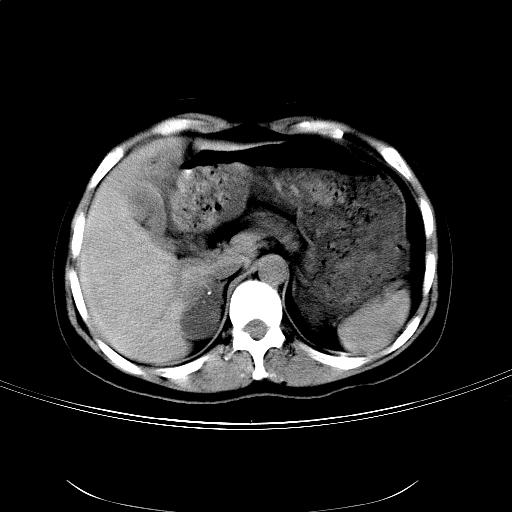

女,36岁,右上腹不适数天。5天后公布结果。

肝左叶有俩原形低密度,边缘光整,内密度均匀一致,考虑小囊肿。

右侧肾上腺区域不规则低密度占位性病变,似乎有俩病灶不完全相连。密度不均匀,内见钙化。首先考虑囊肿,建议增强薄层扫描。

支持1肝内小低密度灶考虑多系囊肿。2右侧肾上腺区低密度结节影,其内见两个小点状钙化灶,低密度影似有分叶或为两个,右肾上部显示不清。考虑右侧肾上腺良性占位病变,请结合临床及超声与增强检查。

比较典型的右侧肾上腺囊肿;肝脏左外叶上段小囊肿。

结果:肾上腺囊肿。